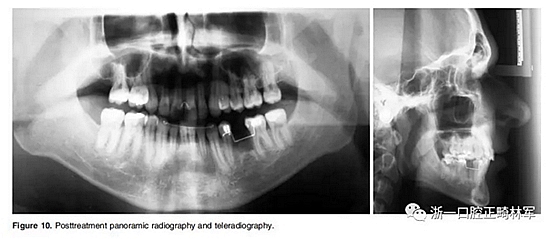

全景片顯示牙根平行度良好、無吸收。此外,在左下第二前磨牙的區(qū)域獲得了用于植入種植體修復的良好空間。頭顱側(cè)位片和疊加顯示,上下切牙傾斜度以及前后和垂直向位置的變化也很大(Figure 10、11; Table 1)。